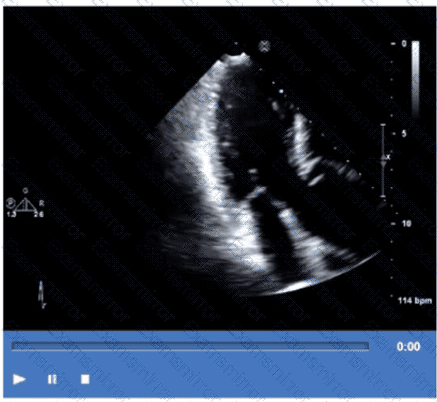

Which finding is best demonstrated in this video?

Which coronary artery territory is associated with the wall motion abnormality demonstrated in this video?